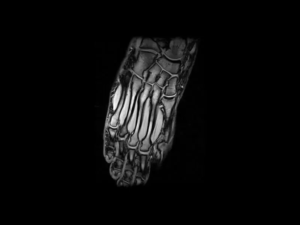

G-SCAN BRIO introduces a pioneering approach tailored for MSK MRI, focusing on enhancing diagnostic accuracy and confidence in evaluating musculoskeletal anatomy and pathology. Its advanced features, such as smooth positioning and dedicated coils, optimize exam performance, making it an ideal choice for orthopedic assessments. By employing MSK MRI machine protocols, G-SCAN BRIO enables clinicians to capture high-resolution images of bones, joints, and soft tissues, facilitating comprehensive evaluations and informed treatment decisions.

G-scan – Foot GE T1 Coronal